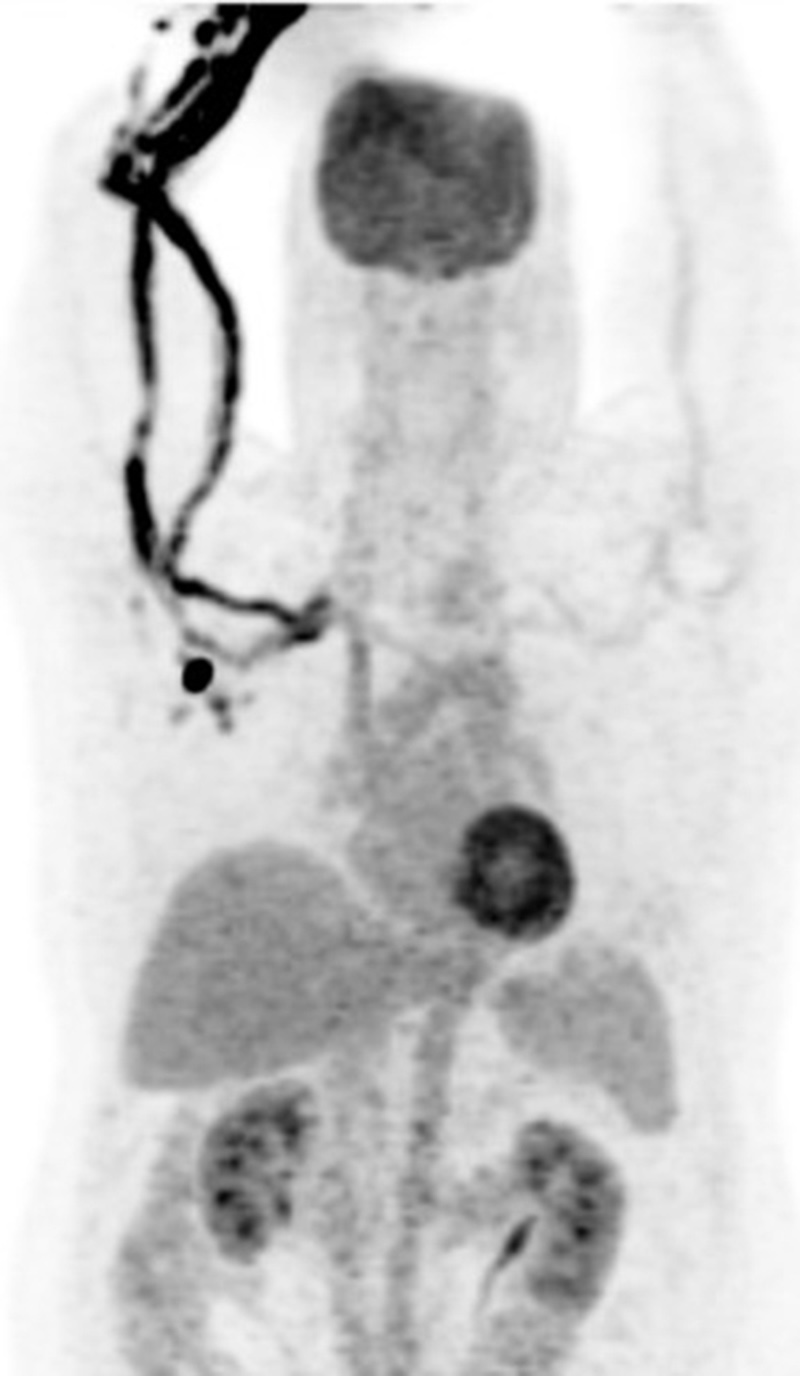

Brown fat or brown adipose tissue (BAT) and white adipose tissue are the two kinds of fat (adipose tissue) found in mammals. Brown fat is especially abundant in newborns with its primary function being to generate body heat. Brown fat cells contain many small droplets of lipids and a high number of mitochondria which make it brown. It contains more capillaries than white fat having a greater need for oxygen delivery. Brown fat becomes less common as one ages. It is still present in adults in the upper chest, neck, paraspinal, and suprarenal regions and is more metabolically active with cold exposure (figure 34).

30 year-old woman with history of lymphoma. Axial CT, PET, PET-CT fused, and PET MIP images demonstrate intense FDG activity in the bilateral neck and paravertebral regions with a symmetrical distribution. Cross-sectional images clearly show that activity in the neck corresponds to fat and therefore consistent with brown fat activity. Brown fat activity is seen more commonly in younger patients and is also increased in response to hypothermia (so keep patients warm both pre and post injection of FDG). |